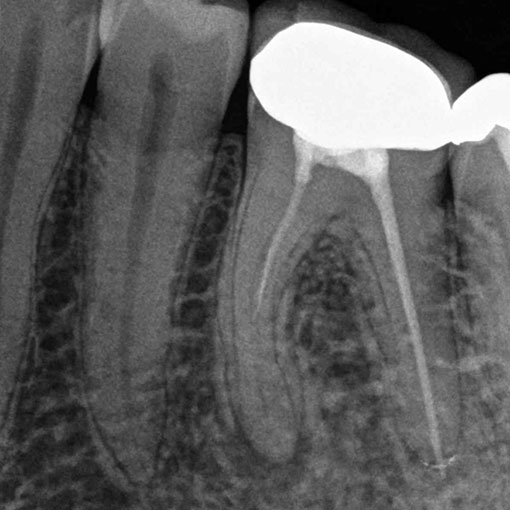

Wurzelspitzenresektion:

Wenn an einer Zahnwurzel eine Entzündung besteht, trotz korrekter vorangegangener Wurzelbehandlung, kann sich dort eine Fistel mit Gang zum Mundvorhof oder eine Wurzelzyste bilden. Auch andauernde Aufbissschmerzen nach abgeschlossener Wurzelbehandlung weisen auf eine Entzündung an der Wurzelspitze hin. Soll der Zahn erhalten werden, muss die entzündlich veränderte Wurzelspitze operativ entfernt werden. Dazu wird das Zahnfleisch im Bereich der Wurzelspitze weggeklappt, und der über der Wurzelspitze befindliche Knochen abgetragen. Das kann auf Wunsch besonders schonend mit dem LASER erfolgen. Dann wird die Wurzelspitze abgetrennt. Auch das kann mittels LASER – Technologie erfolgen. In seltenen Fällen wird die Wurzelschnittfläche zusätzlich „von unten“ abgedichtet. Das Zahnfleisch wird darüber wieder vernäht.